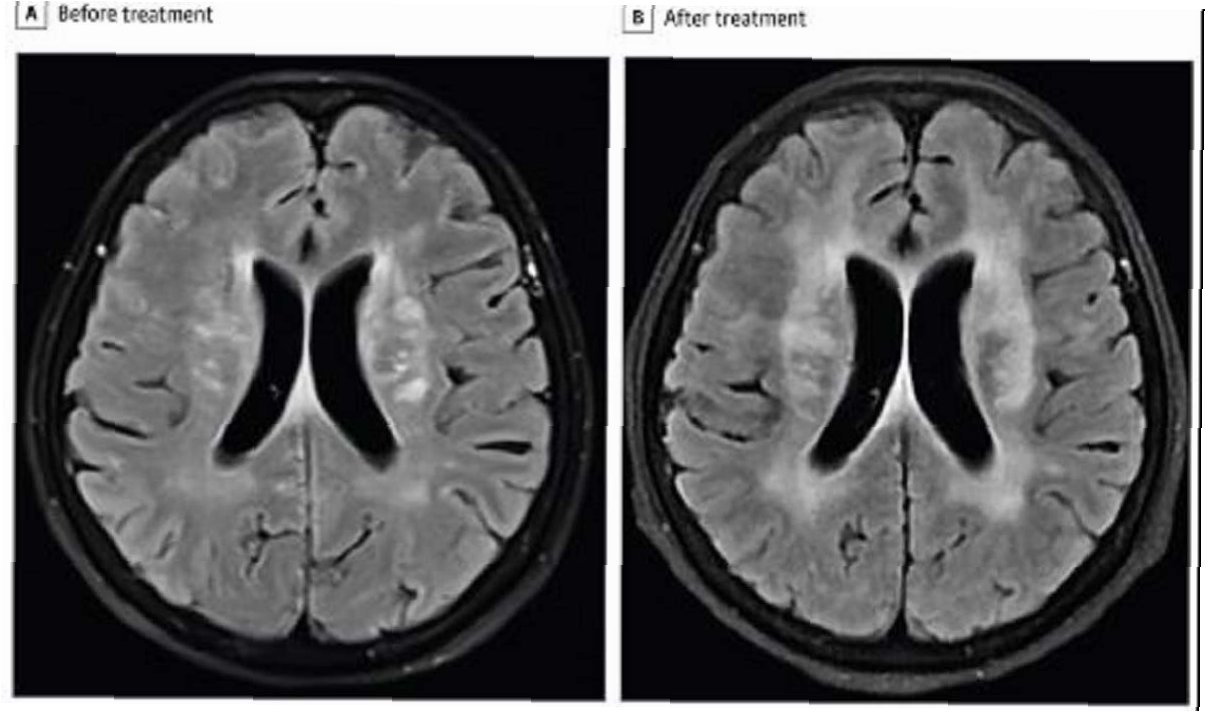

극심한 복통을 호소하며 병원으로 이송된 장씨는 검사 결과 기생충 감염으로 확진되었습니다. 의료진은 소화기관 손상과 함께 스파르가눔을 포함한 기생충이 체내에서 발견되었다고 밝혔습니다. 스파르가눔은 기생충 유충 단계를 의미하며, 이는 장씨가 겪은 고통의 원인이 되었습니다. 이 사건은 개인의 건강을 위해 과학적인 근거 없는 민간요법을 맹신하는 것이 얼마나 위험한지를 보여줍니다.

우중원 의사는 개구리 가죽을 몸에 붙이면 피부병이 낫는다는 소문은 근거가 없으며, 오히려 기생충이 인체에 침투하여 시력 저하, 두개강 내 감염, 생명까지 위협할 수 있다고 경고했습니다. 그는 건강에 대한 잘못된 정보가 얼마나 위험한 결과를 초래할 수 있는지 강조하며, 과학적인 근거를 바탕으로 건강 관리를 해야 한다고 조언했습니다. 전문가의 경고는 건강에 대한 올바른 정보를 습득하고, 검증되지 않은 민간요법에 의존하지 않도록 하는 데 중요합니다.